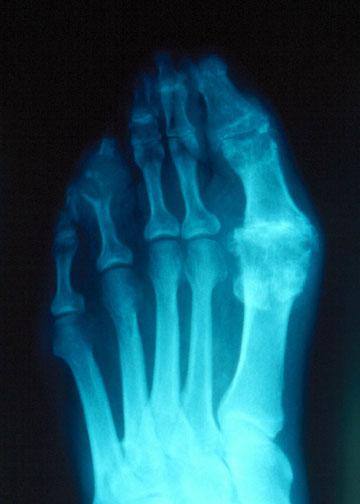

Подагрический артрит с поражением 1 плюсне-фалангового сустава

формалина, чтобы можно было различить и другие кальцификаты, образовавшиеся не из мочевой кислоты. С помощью рентгенологического исследования можно увидеть хондрокальциноз ( кальцификацию хряща в суставах) и подкорковые кисты, которые могут быть связаны с подагрой.

Рентгенограмма изменений 1 плюсне-фалангового сустава при подагре